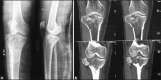

Figure 1A

(a) X-rays of knee joints anteroposterior and lateral views (b) Computed tomography scan coronal images showing Type C bicondylar tibial plateau fractures